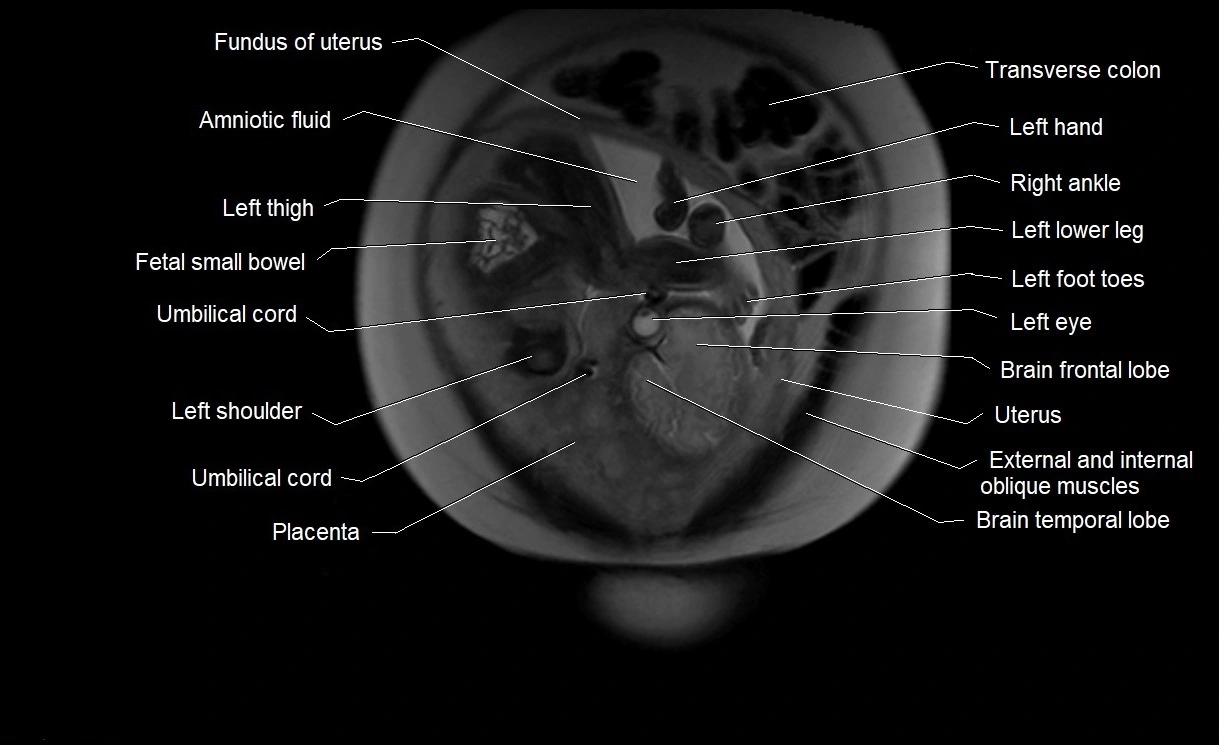

MRI Appearance

T2 HASTE (T2 GRE):

• Amniotic fluid shows very bright hyperintense signal

• Provides natural contrast against fetus and placenta

• Small particles (vernix) may appear as scattered hypointense foci within bright fluid

T1 GRE:

• Amniotic fluid shows low signal intensity (dark)

• Hemorrhage, infection, or proteinaceous content may cause focal or diffuse high signal intensity